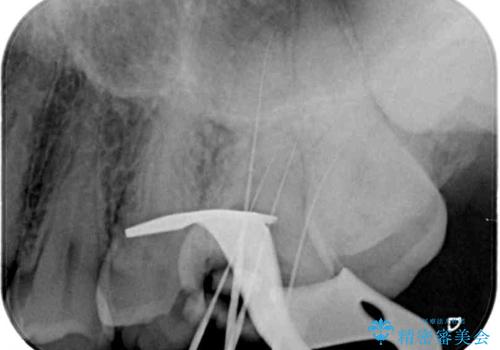

- ラバーダムや顕微鏡を用いた根管治療を希望されて、転院された患者様です。

前医にて神経を取り除いた処置を行った際、ラバーダムが使用されなかったとのことで転院されてきました。

根管治療を実施した後、フルジルコニアクラウンに補綴することとしました。